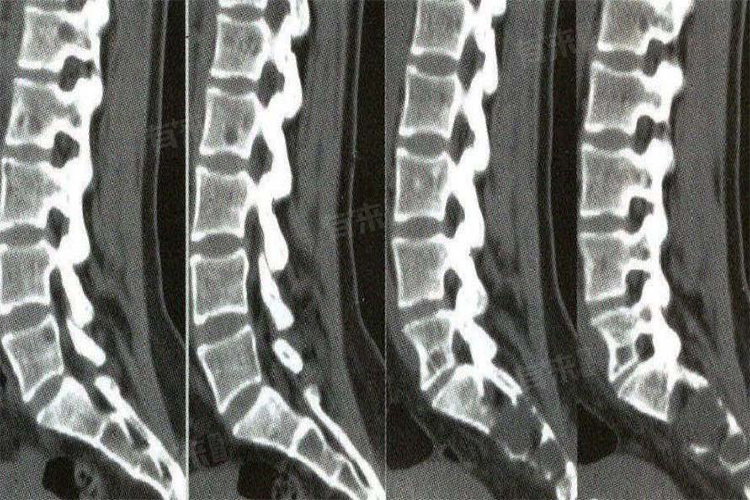

- 检查项目:腰部CT检查包括腰椎平扫、增强扫描、三维重建等多种项目。如果只是单纯的腰椎平扫,价格相对较低;如果需要进行增强扫描或三维重建等特殊检查,费用则会相应增加。